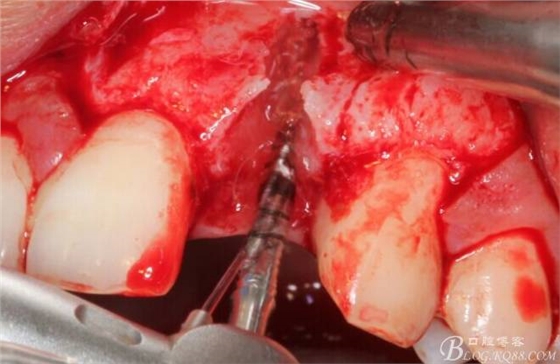

徹底搔刮拔牙窩,偏腭側(cè)備洞

于是我果斷告知患者,手術(shù)失敗了,不能拖延,如不及時(shí)處理,炎癥繼續(xù)發(fā)展會(huì)很快波及鄰牙牙槽骨?;颊呓邮芪业慕ㄗh。切開(kāi)翻瓣,骨粉及生物膜消失了,骨吸收嚴(yán)重,幸運(yùn)的是,因?yàn)樘幚砑皶r(shí),鄰牙骨支持依然存在。

徹底掻刮。